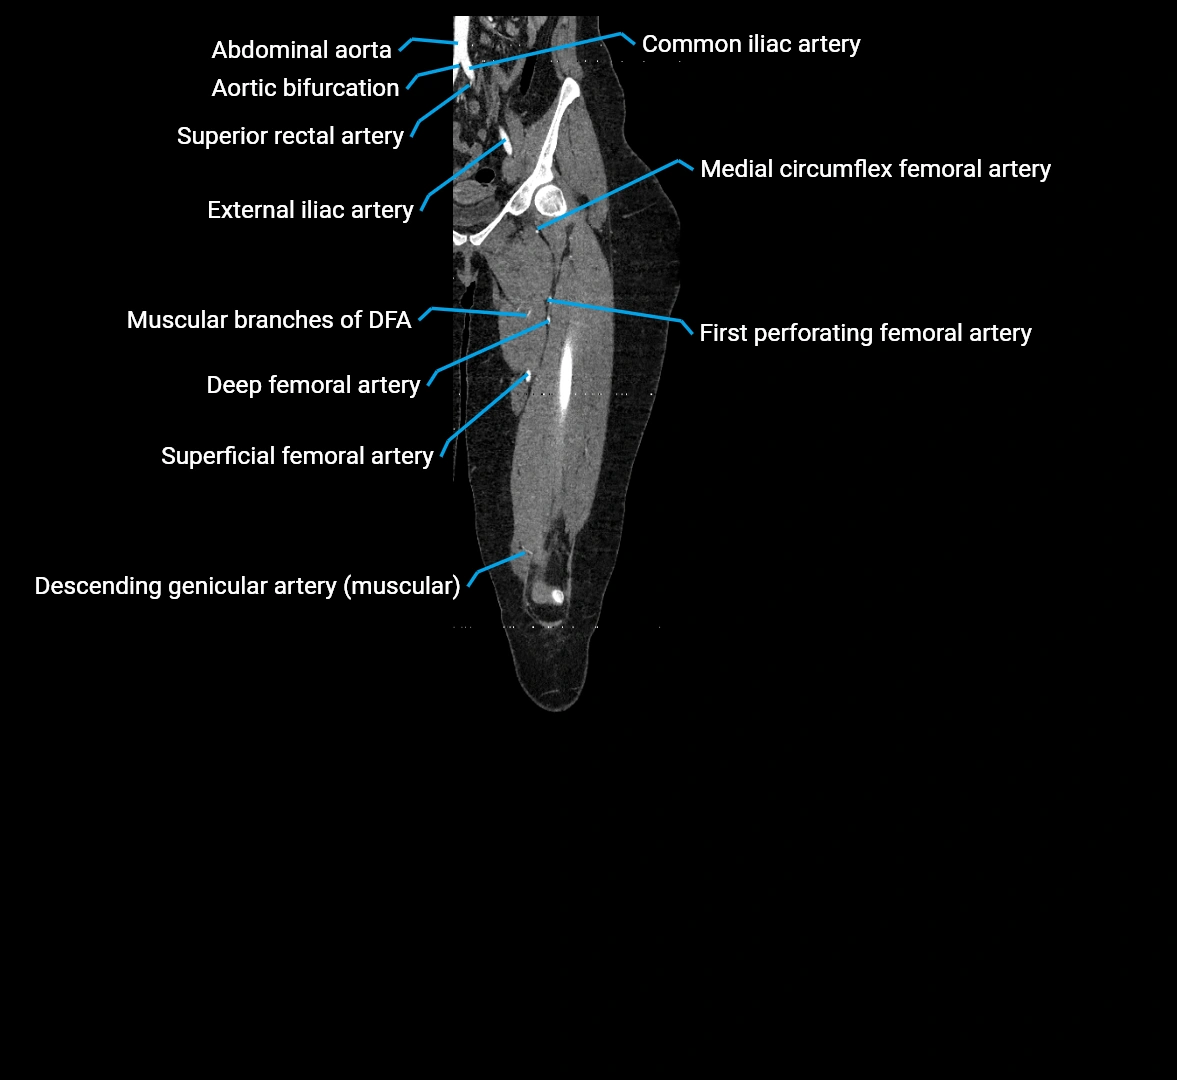

CT images

image

Contrast-enhanced CT (CTA):

• Gold standard for abdominal aortic imaging

• Provides excellent detail of lumen, wall, aneurysm, thrombus, and branch vessels

• Multiplanar and 3D reconstructions help in aneurysm measurement, stent graft planning, and dissection evaluation